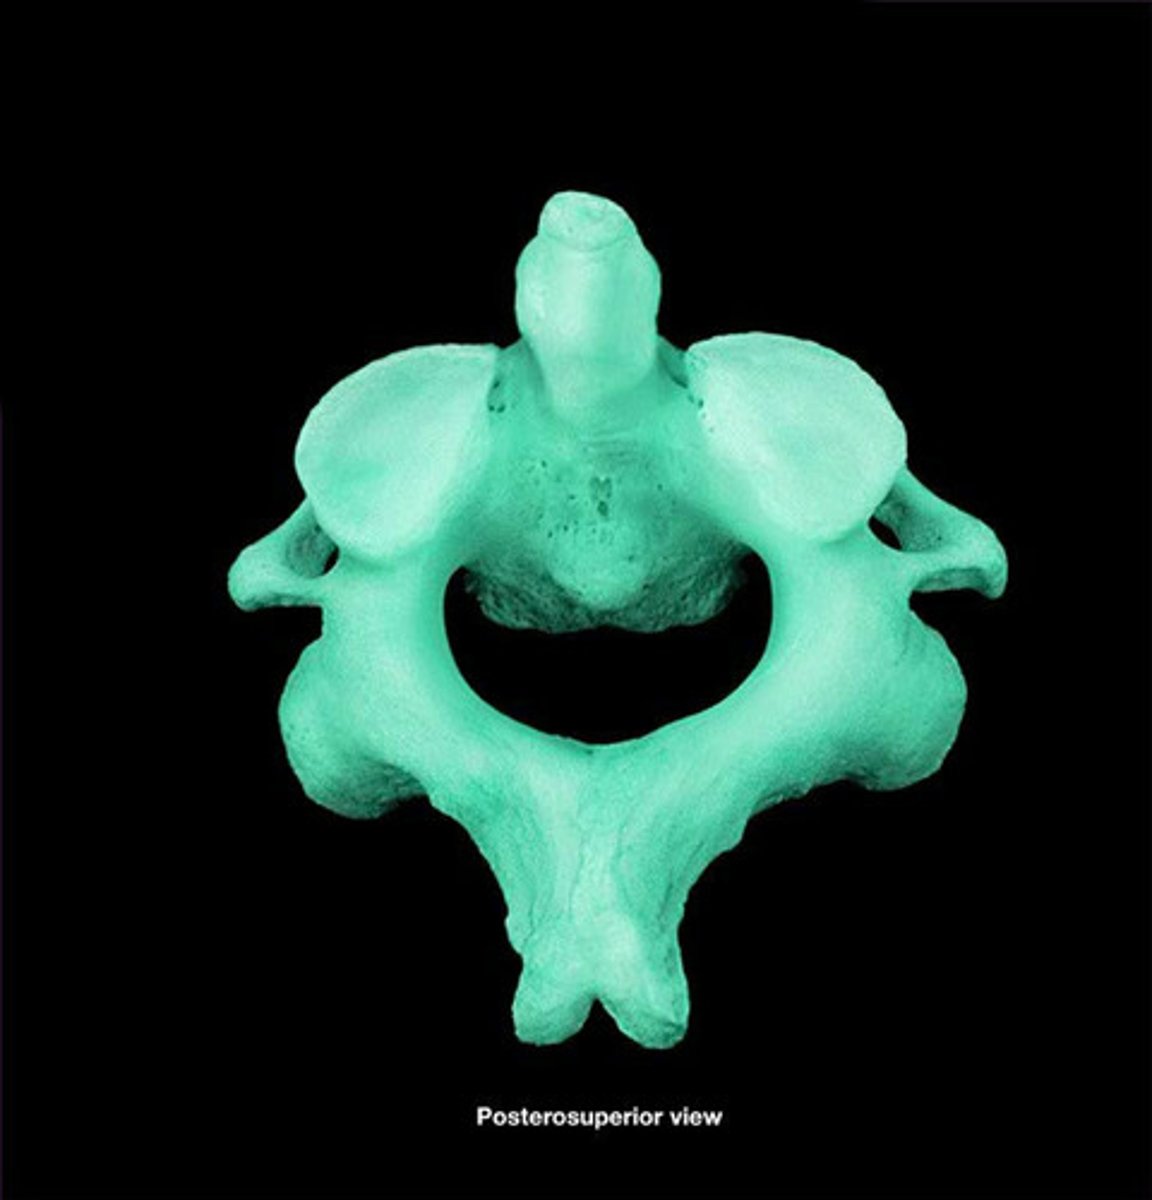

Axis

"no motion"

dens (odontoid process)

Spinous Process of axis